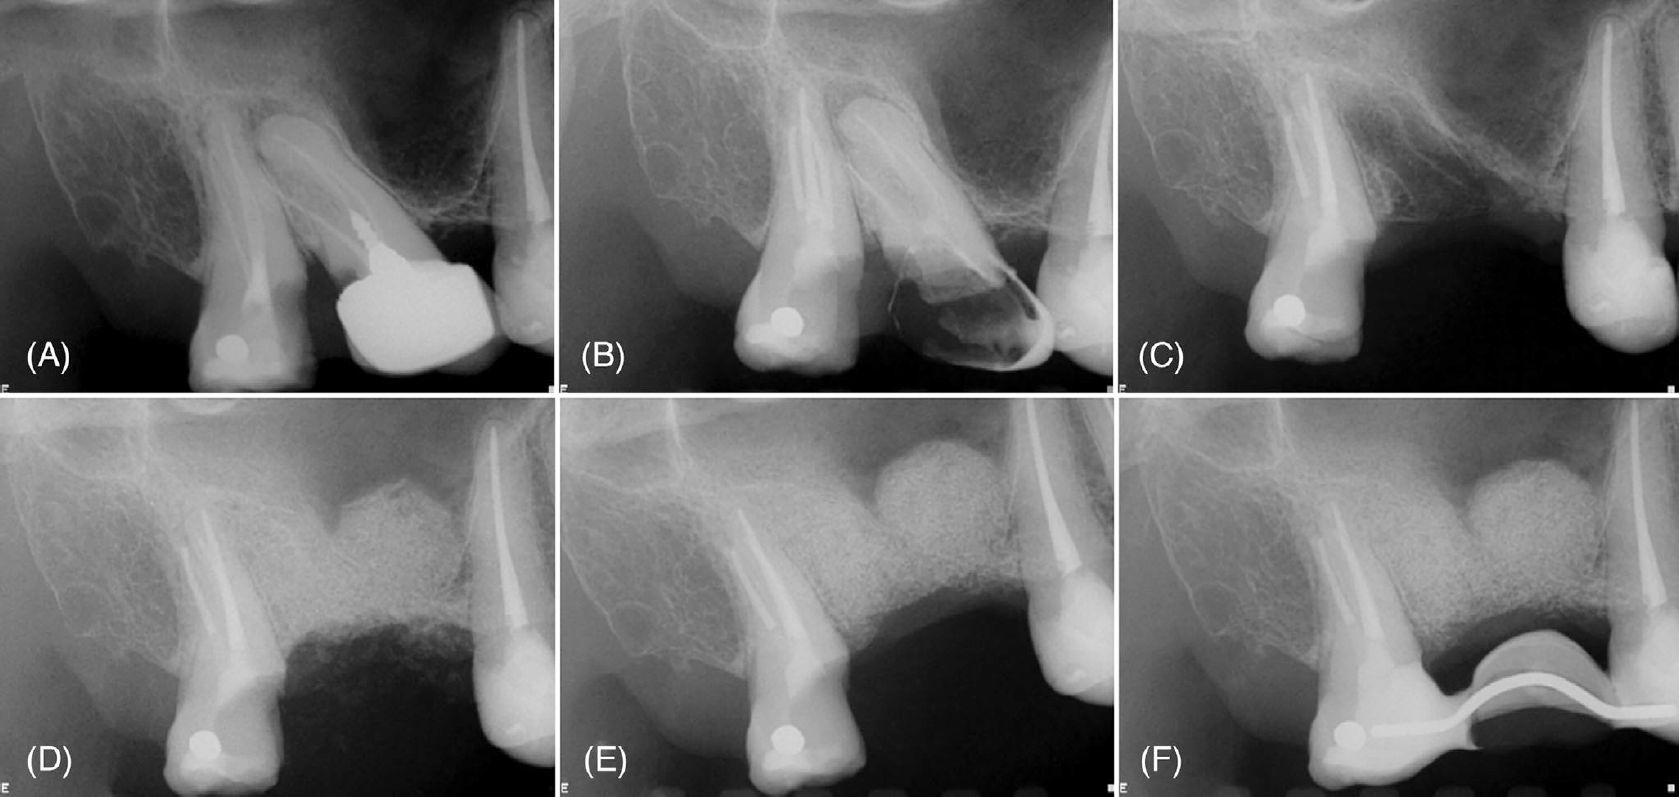

Фото 1. (A) Периапикальные рентгенограммы зуба 17 с рентгенопрозрачным очагом, окружающим корни, и (B) состояние после эндодонтического лечения корневых каналов. (C) Интраоперационная рентгенограмма после ретроградного препарирования и пломбирования щёчных каналов и полной резекции небного корня. (D) Непосредственная послеоперационная рентгенограмма после направленной костной регенерации. Рентгенограммы через 1 месяц (E) и 14 месяцев (F), демонстрирующие стабильное заживление и заполнение костного дефекта

Фото 4. (A) Периапикальная рентгенограмма, демонстрирующая поражение, вовлекающее зубы 16 и 15. (B) Периапикальная рентгенограмма после эндодонтического лечения зуба 15. (C) Интраоперационная рентгенограмма после удаления зуба 16 и ретроградного пломбирования зуба 15. (D) Непосредственная послеоперационная рентгенограмма после направленной костной регенерации. (E) Рентгенограмма через 1 месяц наблюдения, выполненная после установки временной реставрации зуба 17. (F) Рентгенограмма через 8 месяцев наблюдения

Фото 7. (A) Периапикальная рентгенограмма с рентгенопрозрачным очагом в периапикальной области зубов 18 и 17, кариес, дефектные реставрации и неудовлетворительное эндодонтическое лечение. (B) Периапикальная рентгенограмма после эндодонтического перелечивания зуба 18. (C) Интраоперационная рентгенограмма после удаления зуба 17, кюретажа альвеолы и апикопластики зуба 18. (D) Непосредственная послеоперационная рентгенограмма после костной регенерации и синус-лифтинга. Рентгенограммы через 1 месяц (E) и 3 месяца (F) наблюдения